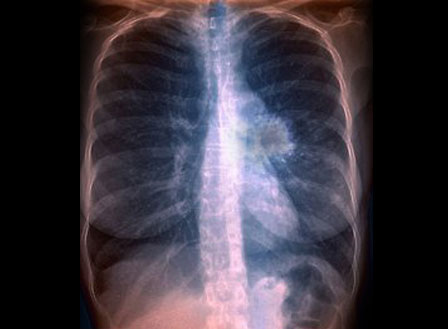

Um novo programa de computador pode ajudar os médicos a eliminar erros no momento de avaliar se uma mancha detectada em uma tomografia de pulmão de um fumante é cancerosa ou não, afirmaram cientistas esta quarta-feira (4).

O método de avaliação de risco clínico, descrito no New England Journal of Medicine, ajudou a decidir corretamente se 9 de 10 manchas eram benignas ou malignas.

Exames de tomografia computadorizada podem salvar vidas, mas são imperfeitos e também podem levar a cirurgias desnecessárias em 25% das vezes, demonstrou o estudo.

Os resultados deste estudo, que se apoia na tomodensitometria, uma técnica de geração de imagens médicas tridimensionais auxiliada por computador, deve permitir melhorar o mau diagnóstico do câncer de pulmão e seu tratamento.

O modelo de análise de risco ajudou a determinar corretamente em 94% dos casos se o nódulo era ou não canceroso, o que os cientistas descreveram como uma “excelente exatidão de previsão”. Além disso, ajudou a diagnosticar pequenos nódulos enganosos com no máximo 10 milímetros em 90% dos casos.